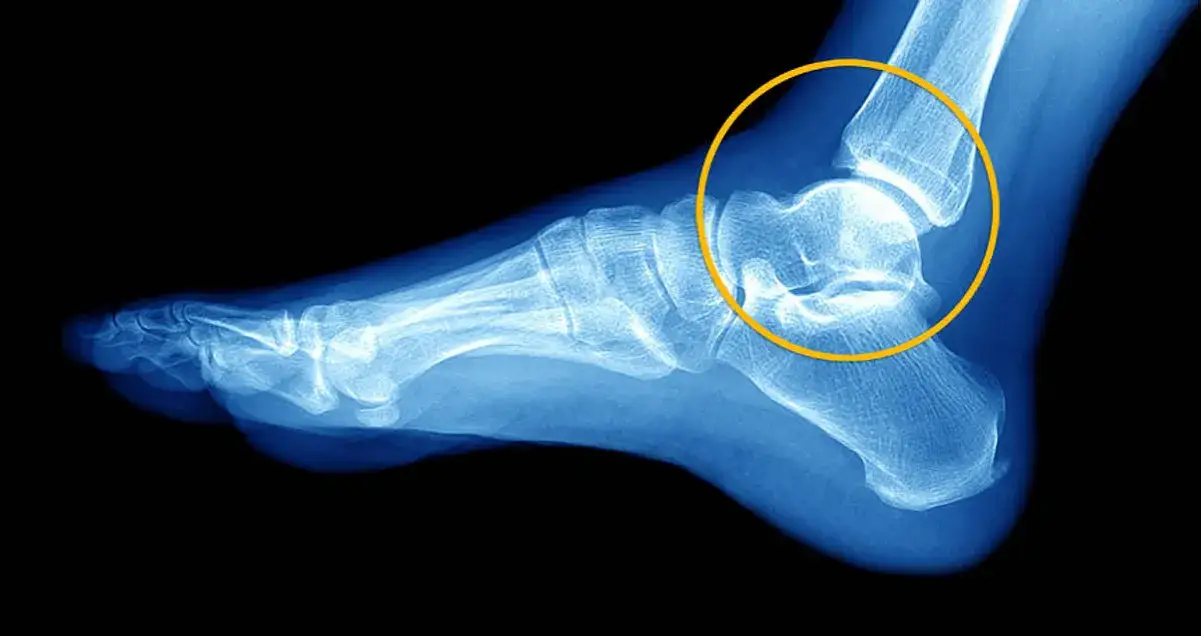

Słyszalny trzask lub chrupnięcie w momencie urazu to objaw, który powinien nas zaniepokoić. Może on świadczyć o poważniejszym uszkodzeniu więzadeł, a nawet o oderwaniu fragmentu kości. Podobnie, jeśli obrzęk narasta bardzo szybko i jest masywny, to znak, że uraz jest rozległy. W takich przypadkach niezwłoczna wizyta u ortopedy jest konieczna. Lekarz prawdopodobnie zleci badanie RTG, aby wykluczyć złamanie, oraz USG, które pozwoli ocenić stan więzadeł i innych tkanek miękkich.Do ortopedy powinniśmy się udać zawsze, gdy podejrzewamy złamanie, uraz jest bardzo bolesny, obrzęk jest duży, a także gdy po kilku dniach stosowania protokołu POLICE nie widzimy żadnej poprawy. Ortopeda postawi precyzyjną diagnozę i zaplanuje dalsze leczenie, które może obejmować unieruchomienie, a w skrajnych przypadkach nawet zabieg operacyjny.